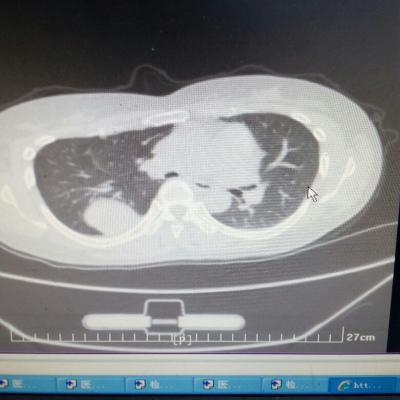

主诉:反酸、烧心5年,加重1年。 病史:患者5年前饮酒出现反酸烧心,并嗳气症状,剑突下烧灼感,饮酒及平卧后加重,无恶心呕吐,无腹痛腹泻,无吞咽困难,服用“达喜”后症状可缓解,易反复发作。3天前我科门诊示:胃镜反流性食管炎(LA-B),现为进一步诊治入院。

1.胃食管反流病 1.1反流性食管炎LA-B 2.食管裂孔疝 处理:患者诊断明确,行腹腔镜下食管裂孔疝修补术+胃底折叠术。

患者术后一周出院,反酸、烧心、嗳气症状明显缓解,无吞咽不畅等症状。 讨论:对于诊断有食管裂孔疝病人的胃食管反流病,且用药有一定疗效,建议行手术治疗,行腹腔镜下食管裂孔疝修补术,修补了膈裂孔,同时行胃底折叠术,加紧了贲门括约肌压力,共同形成抗“反流瓣”。